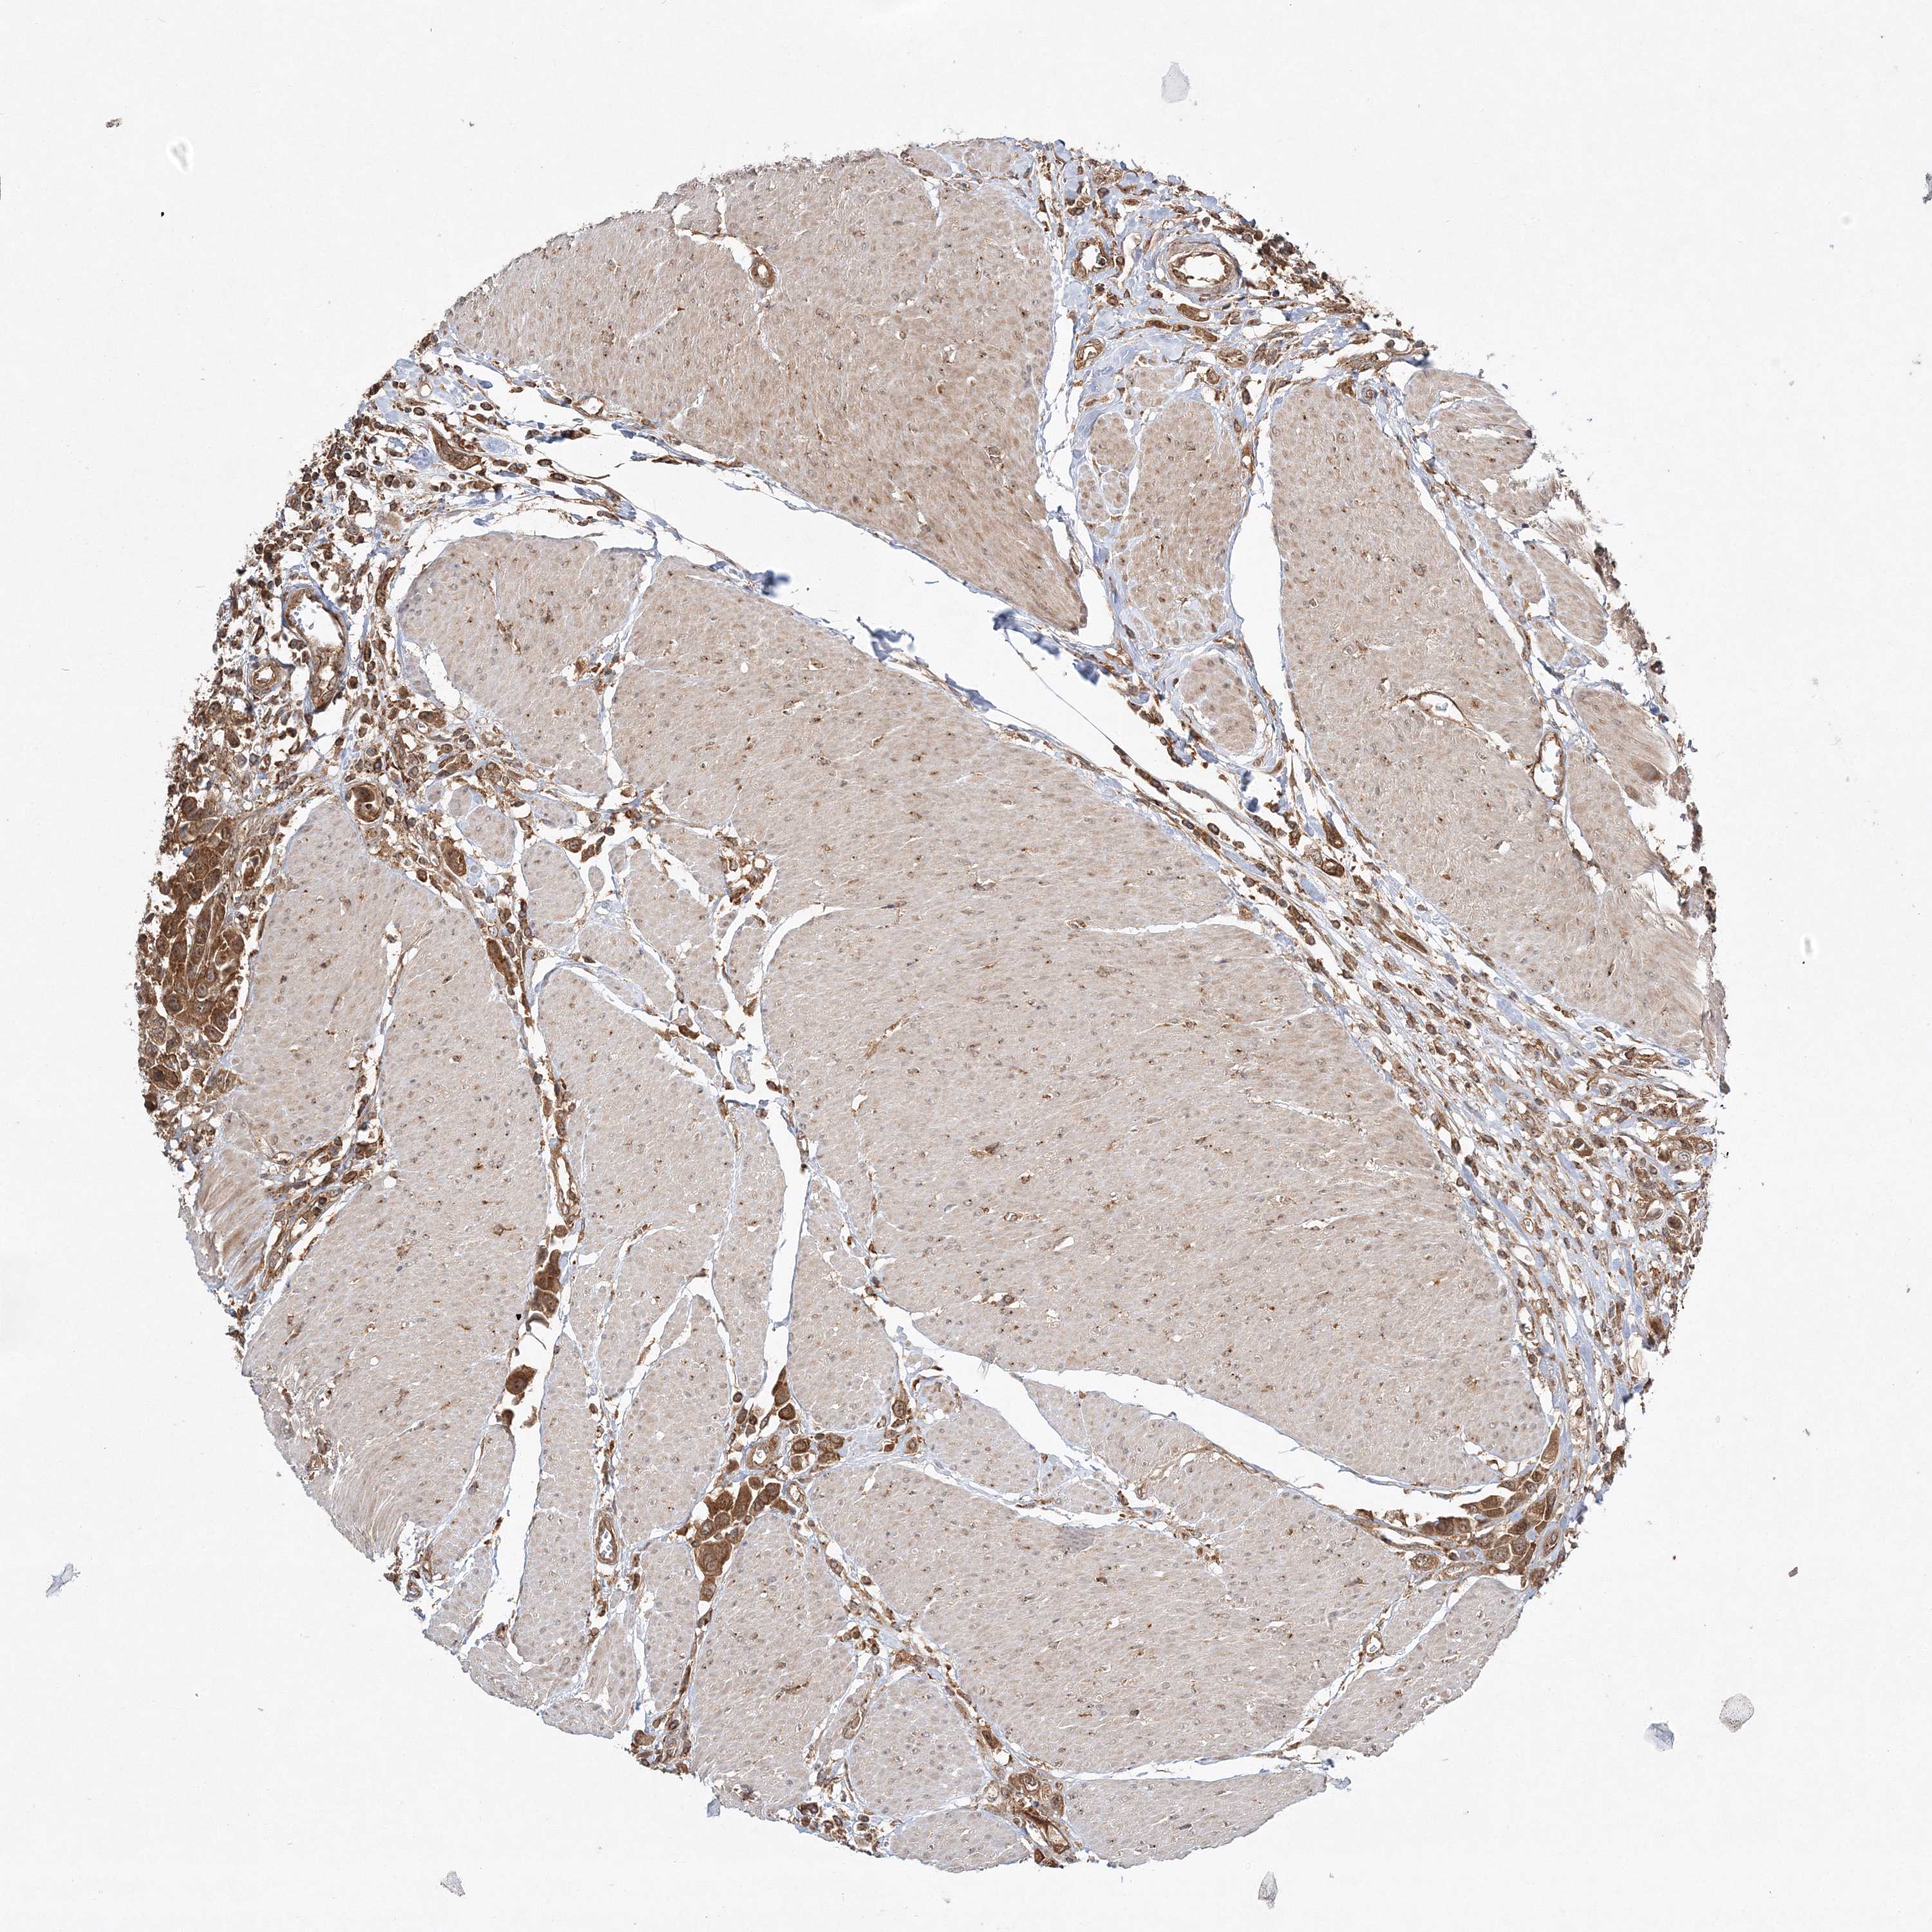

UROTHELIAL CANCER - Protein expressioni

A mouse-over function shows sample information and annotation data. Click on an image to view it in a full screen mode. Samples can be filtered based on level of antibody staining by selecting one or several of the following categories: high, medium, low and not detected. The assay and annotation is described here.

Note that samples used for immunohistochemistry by the Human Protein Atlas do not correspond to samples in the TCGA dataset.

Antibody stainingi

Antibody staining in the annotated cell types in the current human tissue is reported as not detected, low, medium, or high, based on conventional immunohistochemistry profiling in selected tissues. This score is based on the combination of the staining intensity and fraction of stained cells.

Each image is clickable and will lead to virtual microscopy that enables deeper exploration of all samples and also displays staining intensity scores, fraction scores and subcellular localization as well as patient and tissue information for each sample.

Antibody HPA037376

Antibody HPA037565

Staining

High

Medium

Low

Not detected

Intensity

Strong

Moderate

Weak

Negative

Quantity

>75%

75%-25%

<25%

None

Location

Nuclear

Cytoplasmic/membranous

Cytoplasmic/membranous,nuclear

Urothelial carcinoma, Low grade

Urothelial carcinoma, High grade